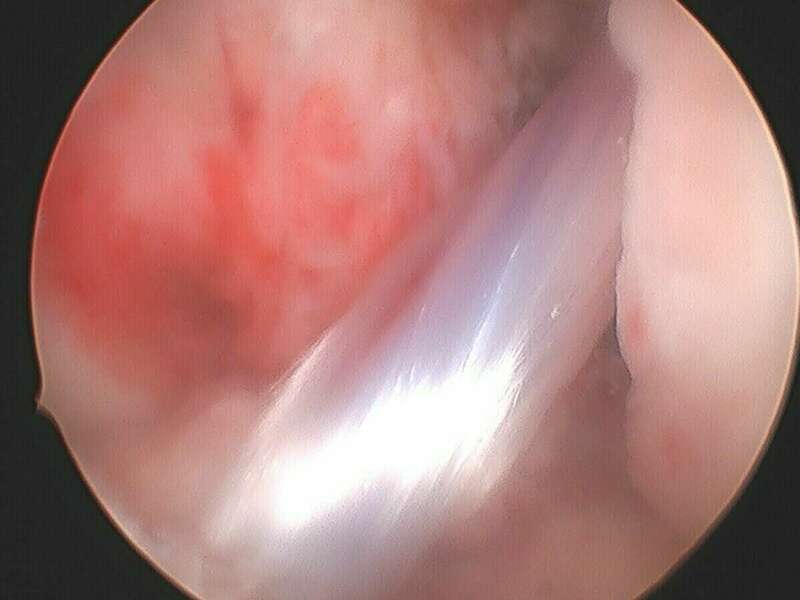

Galerie photo